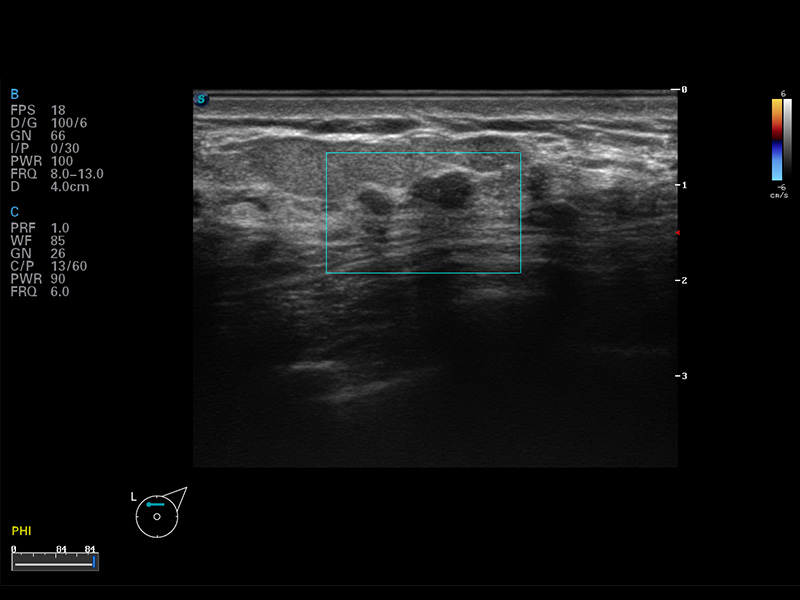

S8 EXP便攜式彩色多普勒超聲診斷儀是開立醫(yī)療研發(fā)的高端全身應(yīng)用型便攜彩超。高通道的VIS平臺(tái)融合可視化(Visual)、智能化(Intelligent)和人性化(Smart)的特點(diǎn),配以開立醫(yī)療自主研發(fā)生產(chǎn)的探頭大家族,使您能夠快速、準(zhǔn)確的獲得病人信息,提高工作效率的同時(shí)減輕疲勞。

成像技術(shù)

μ-Scan微米成像

諧波成像

空間復(fù)合成像